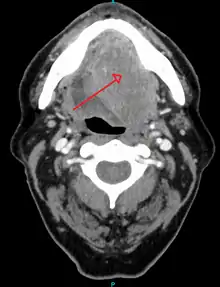

A large squamous cell carcinoma of the tongue as seen on CT imaging

Diagnosis of oral cancer is completed for (1) initial diagnosis, (2) staging, and (3) treatment planning. A complete history, and clinical examination is first completed, then a wedge of tissue is cut from the suspicious lesion for tissue diagnosis. This might be done with scalpel biopsy, punch biopsy, fine or core needle biopsy. In this procedure, the surgeon cuts all, or a piece of the tissue, to have it examined under a microscope by a pathologist.[34] Brush biopsies are not considered accurate for the diagnosis of oral cancer.[35] Salivary biomarkers are also being under investigation with emerging outcomes and could potentially be used as a non-invasive diagnostic tool in the future.[36]